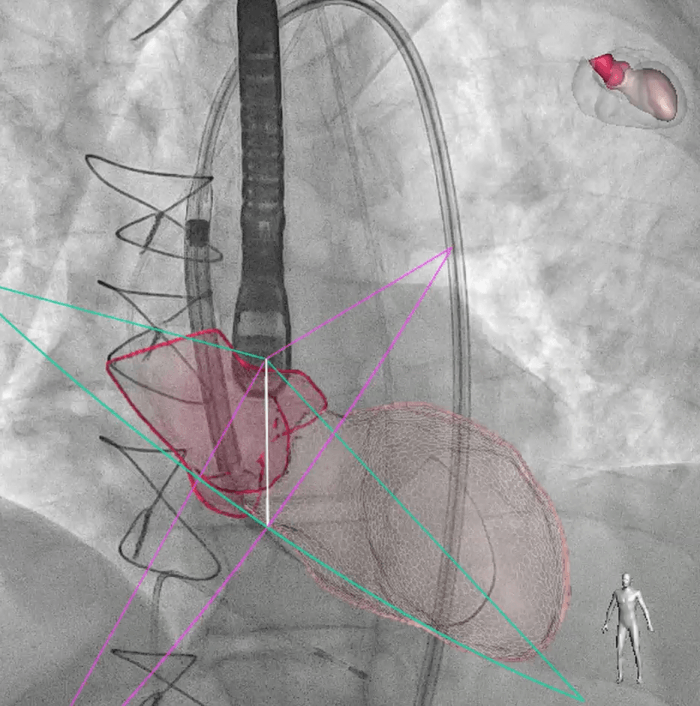

Nous nous intéressions ce midi à l’innovation dans le domaine de la santé avec le Professeur Lancellotti (ULiège et chef du service de cardiologie,CHU ), spécialiste des maladies valvulaires. Avec pour titre « La cardiologie au cœur de la recherche », l’exposé du Professeur s’inscrivait particulièrement bien dans notre volonté de mettre en avant les approches thérapeutiques de demain. La fréquence des maladies valvulaires augmente en effet avec l’âge (en particulier en ce qui concerne les valves aortiques et mitrales) et demain, le Professeur Lancellotti prédit l’implantation de plus d’un million et demi de valves par an.

Améliorer la prévention, le diagnostic, et la prise en charge des patients, tels sont les objectifs de la médecine de demain. Si le marché des dispositifs médicaux implantables, dans le domaine cardiovasculaire, est très vaste, qu’il tend à se développer et que ce secteur est très innovant, on sait que l’utilisation de ces dispositifs peut être associé à la survenue d’infections difficiles à traiter ainsi que de complications thrombotiques.

Pour parer à ces difficultés et améliorer la prise en charge des patients, le Professeur travaille depuis de nombreuses années, avec son équipe, d’une part, au développement d’un coating universel permettant d’améliorer la sécurité et la durabilité des valves cardiaques artificielles ou biologiques ou de tout autre implant cardiovasculaire. La technologie utilisée permet d’obtenir des nano-réservoirs chargés de médicaments à relargage progressif. Les premiers tests sur des valves cardiaques sont très concluants. Actuellement, la technologie est en voie d’adaptation pour les cathéters (ERC Proof of Concept, CMD-COAT project).

D’autre part, le groupe de recherche s’intéresse également au développement de valvules cardiaques prothétiques personnalisées, imprimables en 3D, à base d’un polymère « vert » innovant.

Améliorer la prévention, le diagnostic, et la prise en charge des patients, tels sont les objectifs de la médecine de demain. Face à ces enjeux, les dispositifs médicaux apportent des solutions innovantes dans de nombreux domaines comme la cardiologie (stimulateurs ou valves cardiaques), l’orthopédie et la rhumatologie (prothèses articulaires et matériel d’ostéosynthèse), la chirurgie de reconstruction (prothèses mammaires) ou l’oncologie (cathéters de longue durée pour l’administration de chimiothérapie anticancéreuse). Le marché des dispositifs médicaux est donc très vaste et le secteur très innovant. Le tissu industriel est multiple et diversifié, comprenant à la fois de grandes multinationales et de toutes petites PME.

L’utilisation de ces dispositifs est toutefois associée à la survenue d’infections ayant comme caractéristiques communes d’être difficiles à traiter et de survenir chez des patients ayant, en règle générale, plusieurs comorbidités. Les dispositifs médicaux au contact de sang sont également sujet aux complications thrombotiques, ce qui contribue aussi aux hospitalisations plus longues, à des coûts de soins de santé plus élevés, voire au décès des patients.

L’équipe du Professeur Lancellotti travaille depuis de nombreuses années, grâce à plusieurs financements européens (ERC Consolidator Grant, PV-COAT project), au développement d’un polymère bioactif (« Coatigel »), combinant des propriétés antimicrobiennes, antibiofilm, et antithrombotiques, pouvant servir de revêtement universel et adhérant sur les dispositifs médicaux. La technologie utilisée permet d’obtenir des nano-réservoirs chargés de médicaments à relargage progressif. Les premiers tests sur des valves cardiaques sont très concluants. Actuellement, la technologie est en voie d’adaptation pour les cathéters (ERC Proof of Concept, CMD-COAT project) et le tremplin de la création d'une nouvelle spin-off dans le bassin Liégeois.